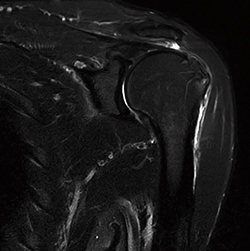

■症例1:RADAR T2強調像FatSat(ECHELON OVAL)

肩関節は,呼吸性のモーションアーチファクトが腱板に重なりやすく,磁場中心から離れているため撮像が難しい。RADARによって動きを抑制し,ワイドボアガントリで肩関節を磁場中心近くにポジショニングできるため画質が向上し,腱板の評価に有用である。

RADAR,T2WI,FatSat,COR,

FOV:160,TR/TE:3421/70,

スライス厚:3mm